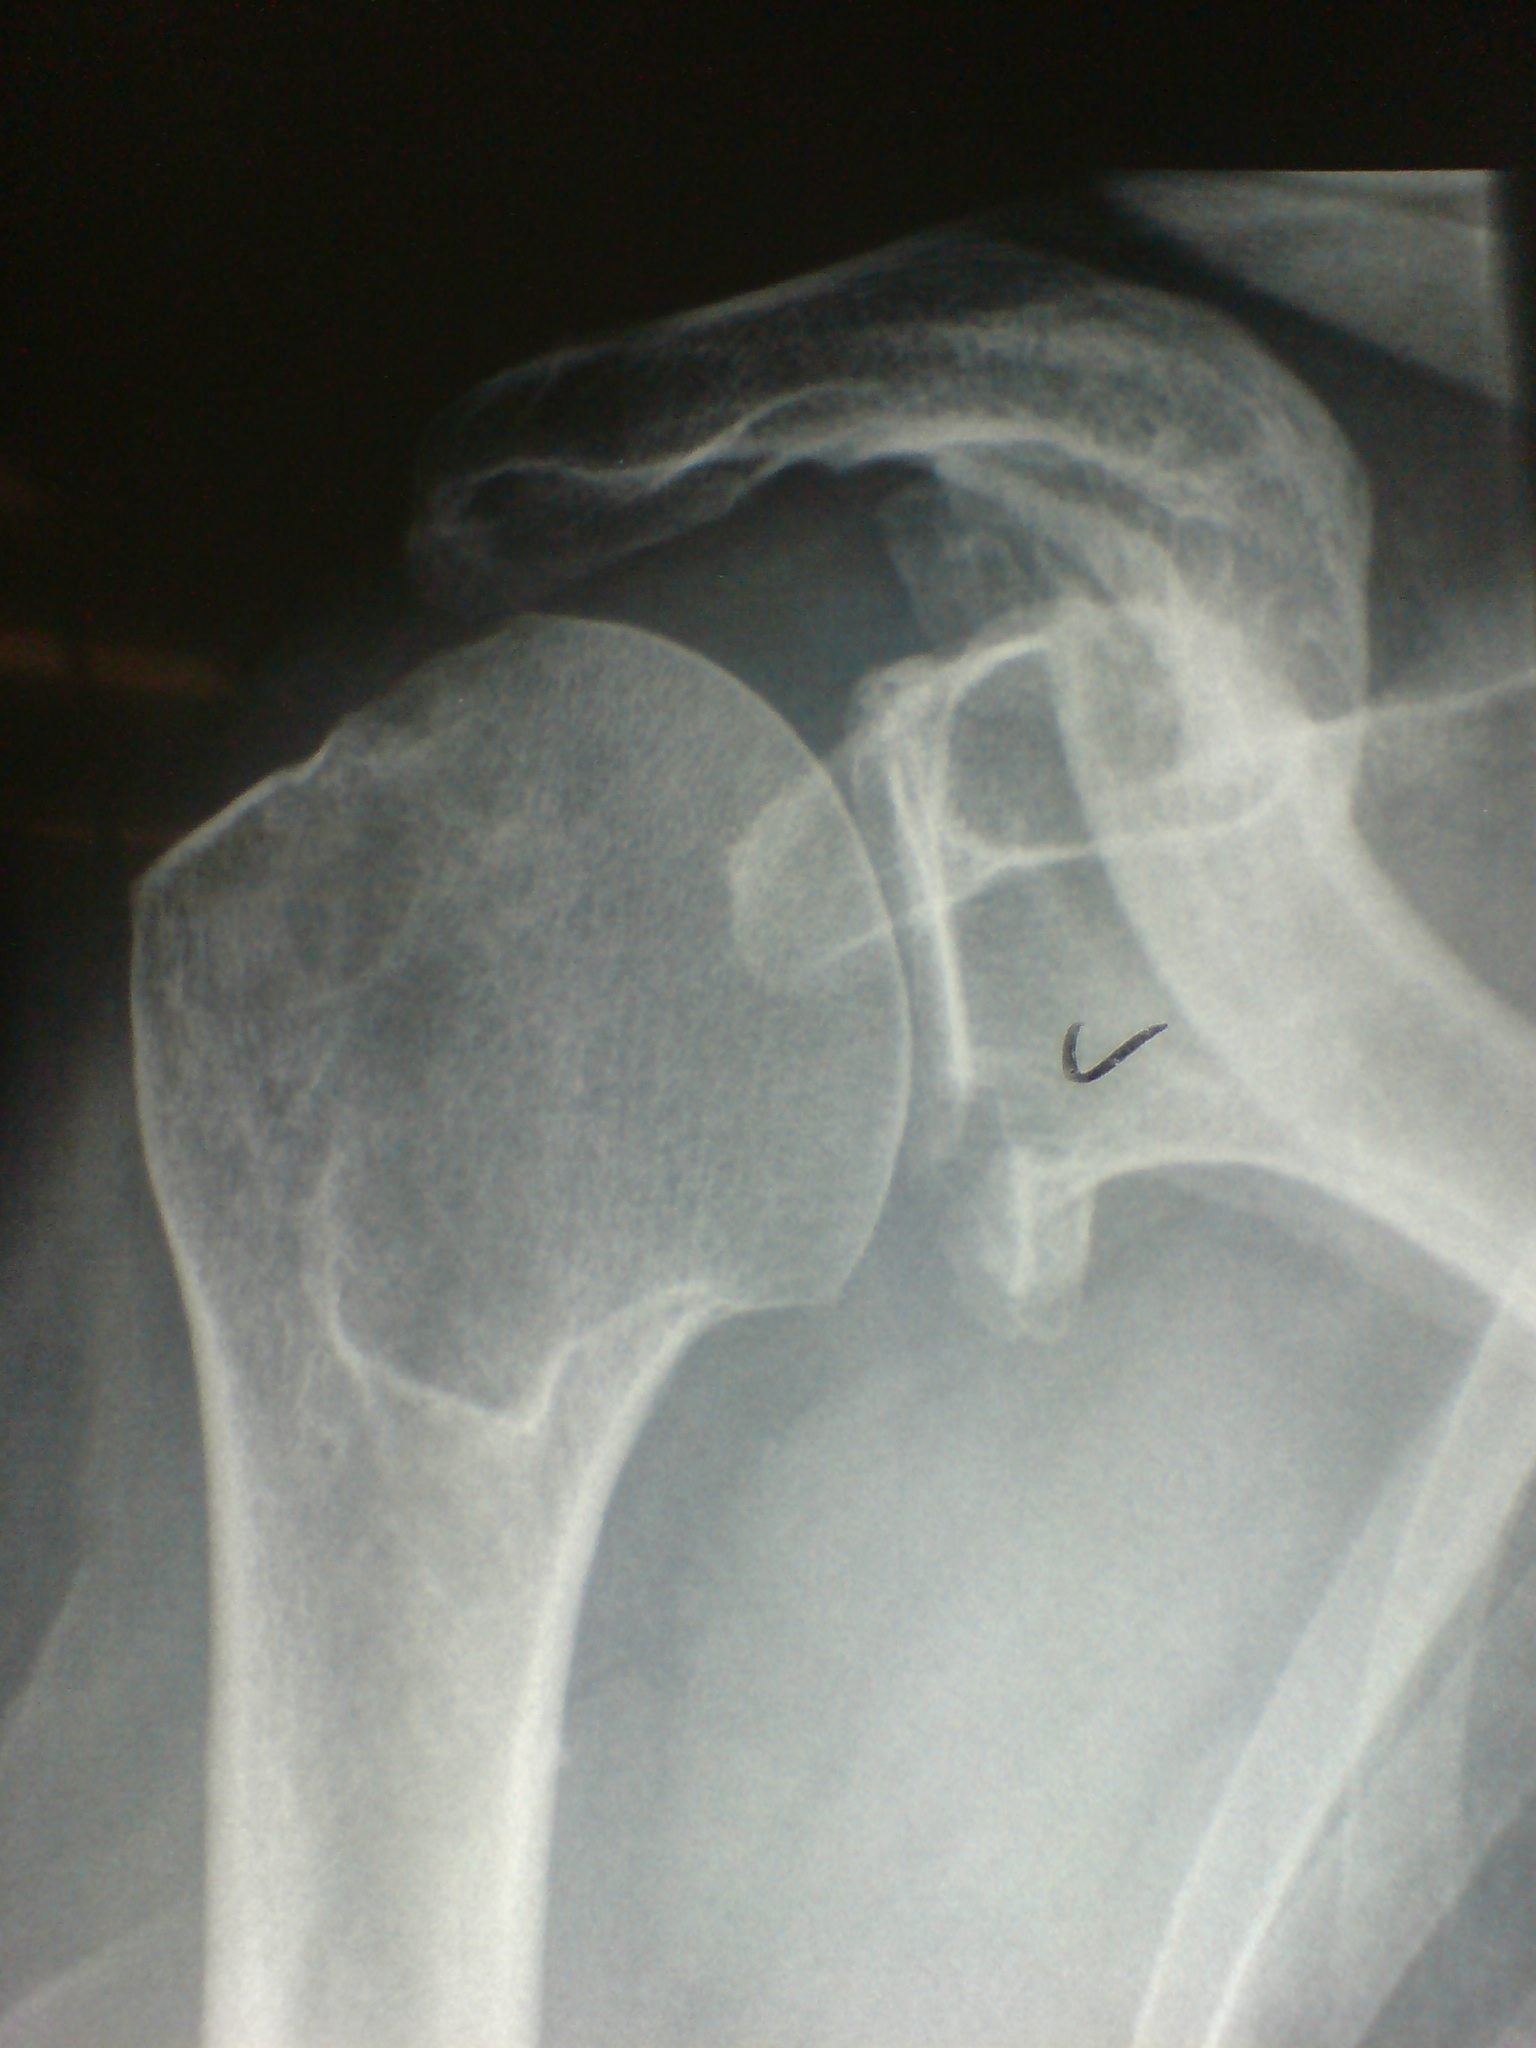

Bony bankart / glenoid rim fractures

Glenoid fossa fractures

- 25 - 30%, displaced

- open v arthroscopic screw fixation

www.boneschool.com/glenoid-fractures